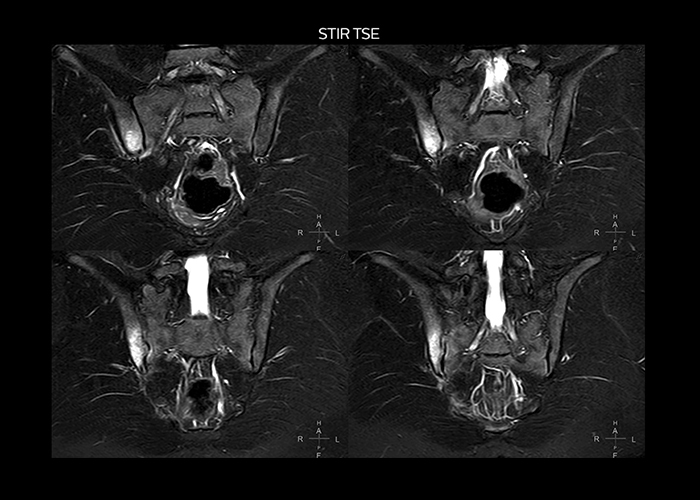

“On average, we scan about 80 patients per day, but on some days we scan well over 100 patients. The scanner is in use 7 days per week, operated 20 hours per day on week days and 8 hours per day in the weekend,” Mr. Tuna says. “To avoid coil changes we plan examinations of similar anatomies back to back, such as head and spine. Multiva helps us here a lot because coils don’t need to be changed frequently. Moreover, thanks to parallel imaging technology and 16-channel HeadSpineTorso and 8-channel MSK coils we are able to achieve excellent image quality. In this way Multiva helped us to increase both image quality and productivity.” “Neurological cases, such as brain and spine imaging, represent the largest share in our MR scanning, followed by musculoskeletal cases. In general, we use simple and basic imaging protocols. But occasionally, we use advanced techniques for problematic cases if necessary.

“Since we have Multiva, we have improved our workflow, because it has been so easy for our operators to learn and use Multiva. Our operators notice that the coils are lightweight and coils don’t need to be changed frequently. The user interface is easy to use. Features like this help us to scan a high number of patients. For instance, the musculoskeletal coils can be used interchangeably, and due to the user-friendly interface, the number of mistakes such as, for example, correct coil element selection has decreased significantly, because the system does it automatically by itself.” “Most important, Multiva satisfies our clinical imaging needs very well,” says Mr. Tuna. “Many features of Multiva have become similar to the Ingenia system. Even in more complex imaging such as abdominal and cardiac, the image quality and performance of Multiva is better than we expected. General surgeons and physicians from our hospital’s internal medicine department prefer to refer to us because of this.”